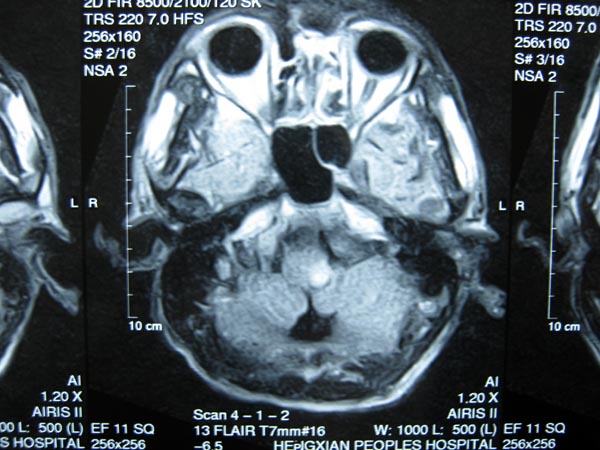

脑干梗塞引起严重吞咽障碍的他再次能够正常进食

覃某某因吞咽困难、饮水呛咳、不能行走3个月来住院治疗。患者家属代诉三月前在钓鱼时无明显诱因下站立起来突然出现头晕,伴视物旋转、胸闷、恶心、声音沙哑、吞咽困难、饮水呛咳。遂在家人陪同下送至当地医院诊治,诊断为“脑干梗塞急性期”,经治疗后仍遗留吞咽困难,声音沙哑、喉间痰鸣,并伴有左侧肢体麻木,出现明显共济失调,不能站立行走。为进一步治疗入住瑞康医院康复中心系统康复治疗。结合患者存在吞咽、运动、语言三个方面的功能障碍,康复中心的医师、康复师通过系统评定给患者制定全面的康复治疗。吞咽方面评定发现患者存在环咽肌开放不全、咽缩肌力量减弱且收缩不对称、喉上抬不充分、声带闭合不充分、软腭上抬不充分且欠协调、咽反射、呕吐反射减弱。运动方面评定发现患者存在较严重的共济失调。